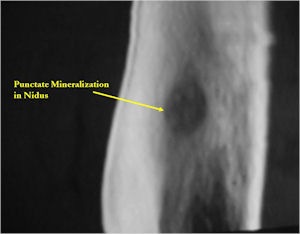

CT Scan:

- Well defined nidus with a smooth peripheral margin; +/- mineralization (CT more sensitive than XR and MRI for detecting mineralization); CT is better for detecting nidus in presence of exuberant sclerosis

- The nidus may demonstrate mineralization/ossification usually from the center outward that appears as a central zone of density within the nidus